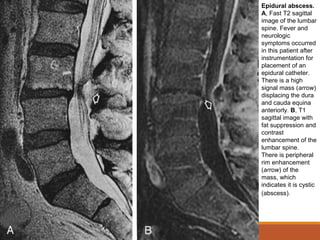

Alterações Inflamatórias

Abscesso Epidural:

◦Extensão direta da infecção por espondilodiscite (80%

dos casos) por causar um abscesso epidural.

◦Outras vezes, há disseminação hematogênica para o

espaço epidural a partir de uma infecção local distante,

ou pode ocorrer implantação direta de bactérias através

de instrumentalização.

◦Dois estágios podem ser evidenciados:

◦ Fleimão (inflamação difusa das partes moles)

◦ Abscesso (coleção de líquido focal).

Epidural abscess.

A, Fast T2 sagittal

image of the lumbar

spine. Fever and

neurologic

symptoms occurred

in this patient after

instrumentation for

placement of an

epidural catheter.

There is a high

signal mass (arrow)

displacing the dura

and cauda equina

anteriorly. B, T1

sagittal image with

fat suppression and

contrast

enhancement of the

lumbar spine.

There is peripheral

rim enhancement

(arrow) of the

mass, which

indicates it is cystic

(abscess).